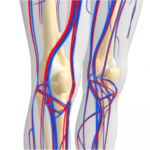

La intoxicación por bloqueadores beta-adrenérgicos es un fenómeno clínico complejo que se asocia a la administración excesiva o inadecuada de fármacos que actúan sobre los receptores beta-adrenérgicos del sistema nervioso…